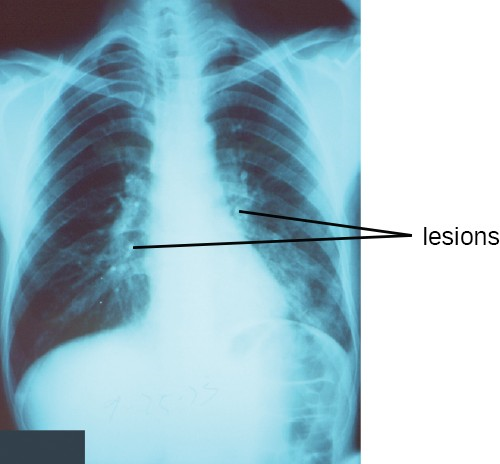

A chest radiograph of a patient with pneumonia shows the consolidations (lesions) present as opaque patches.

Figure 17.8 A chest radiograph of a patient with pneumonia shows the consolidations (lesions) present as opaque patches. (credit: modification of work by Centers for Disease Control and Prevention)